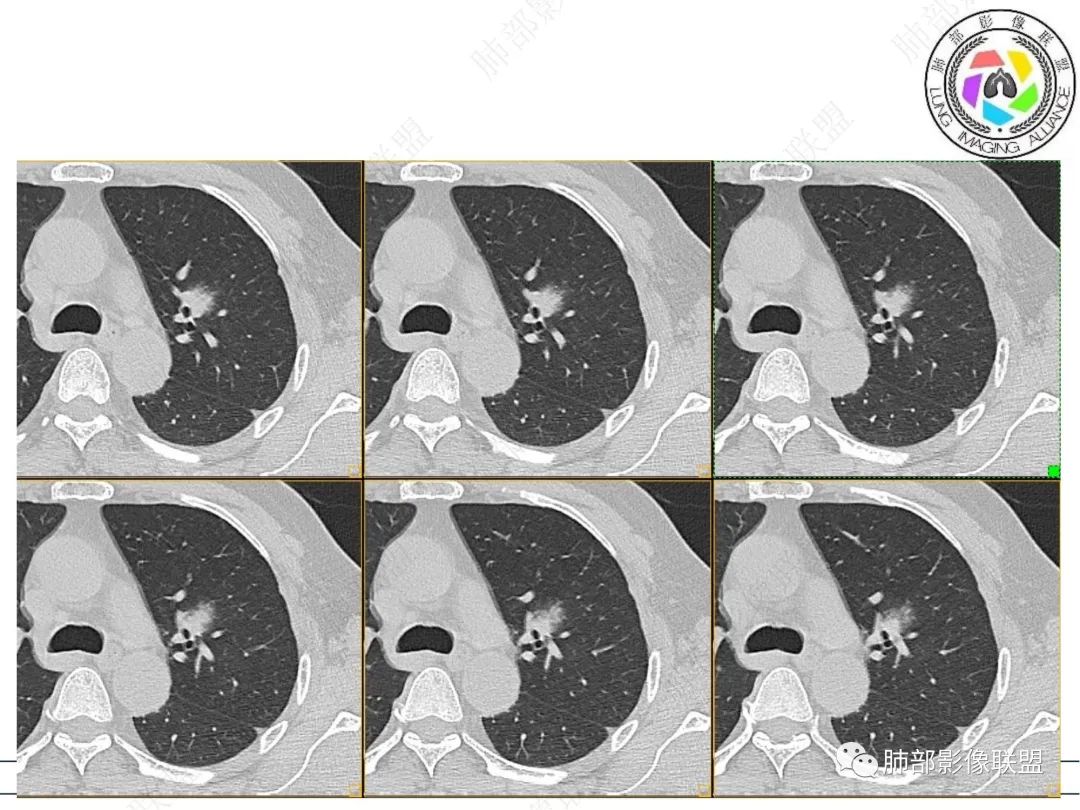

结节逐渐增大并支气管闭塞,边缘磨玻璃,明显强化,考虑腺癌,类癌

@达州红十字医院 尹发友?尹院长,开始的时候支气管变窄的,后面就闭塞了,可否说明是冰山呢

影像表现,结节主体在腔外,局部逐渐累及支气管至堵塞,而且三年逐渐增大,肺门及纵隔未见明显肿大淋巴结,腺癌一般不是这种变化

左肺上叶前段实性结节,沿支气管血管束生长,整体形态近三角形,边缘模糊,累及前段气管主支管壁增厚,管腔通畅,前后复查不足两年病灶倍增明显,肿瘤指标阴性,支持炎性肉芽肿,2019年10月2日首诊图,主体结节外周似有小卫星灶分布,需薄层确认,支气管镜肺泡灌洗检查。

中年男性,无明显不适,左肺上叶前段支气管周围结节,复查逐渐增大,部分膨隆,边缘磨玻璃影内血管影增粗,复查亚段支气管阻塞,不均匀强化,考虑腺癌。

1、连续3年观察,病灶逐步增大,符合惰性恶性肿瘤。2、支气管壁增厚,腔内内壁无变化——病灶长轴沿支气管周围蔓延;朝外走,内侧没有,提示病灶间质为主,与支气管无关。

3、GGO长期存在,朝外蔓延,支持恶性特点。

支持淋巴瘤的关键点:1、间质为主;2、与支气管无关;3、边缘GGO的长期存在支持恶性

因为与支气管无关不支持腺癌,还是要警惕淋巴瘤。